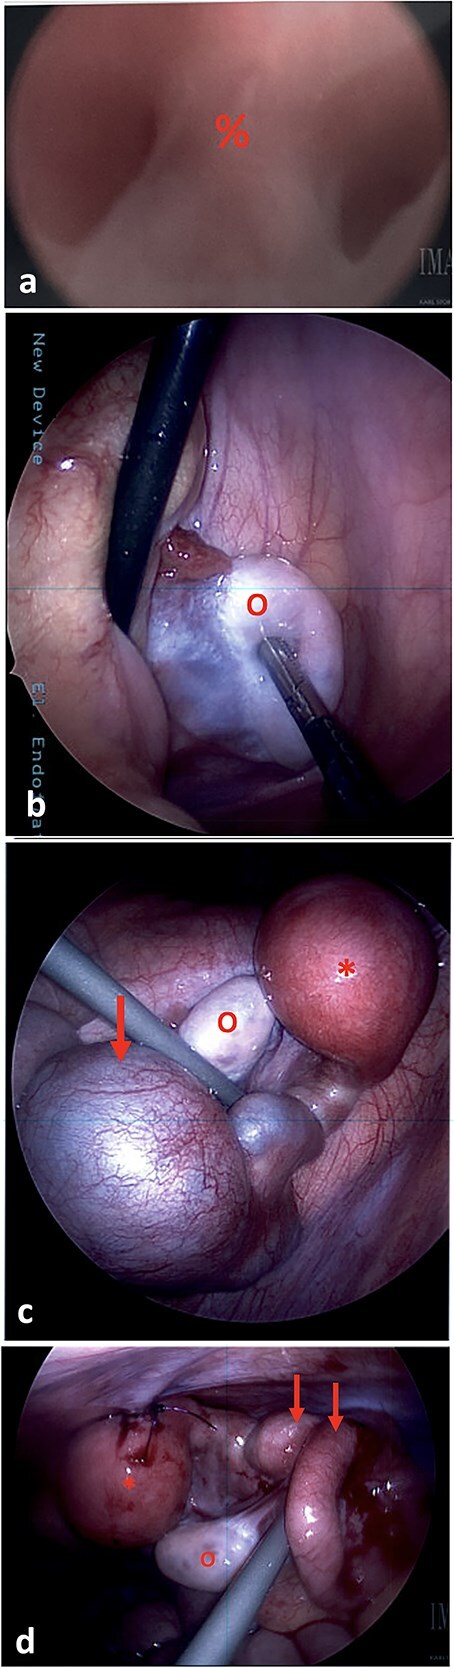

MRKH综合征(mayer - rokitansky - k - hauser综合征)是一种生殖道畸形,发生率约为5000分之一。其特点是先天性发育不全或明显的苗勒管衍生结构发育不全。大约3%的MRKH患者有正常的子宫。一名12岁健康女性,表现为持续周期性严重右下腹疼痛。她被发现有MRKH综合征,右侧子宫功能正常,有子宫积血和同侧输卵管积血。随后,她接受了诊断性膀胱镜检查、阴道镜检查和盆腔腹腔镜检查。腹腔镜下行子宫积血、输卵管积血引流,子宫造口置管及子宫前腹壁固定。术后症状完全消失。2周后的计算机断层扫描显示血肿消退,输卵管积血明显改善。子宫功能正常的MRKH综合征可能表现为青春期女性患者的周期性腹痛。腹腔镜子宫引流放置是一种治疗选择。

Mayer-Rokitansky-Küster-Hauser (MRKH) syndrome is a reproductive tract malformation occurring in ~1 in 5000 female births. It is characterized by congenital agenesis or marked hypoplasia of the Mullerian ducts derivative structures. About 3% of MRKH patients have a functioning uterus. A 12-year-old otherwise healthy female presented with persistent cyclic severe right lower quadrant pain. She was found to have MRKH syndrome with a right-sided functioning uterus and hematometra and ipsilateral hematosalpinx. She subsequently underwent diagnostic cystoscopy, vaginoscopy, and pelvic laparoscopy. Laparoscopic drainage of the hematometra and hematosalpinx, and hysterostomy catheter placement and uterine fixation to anterior abdominal wall were performed. Symptoms fully resolved post-operatively. A computed tomography scan 2 weeks later demonstrated resolution of the hematometra and significant improvement in the hematosalpinx. MRKH syndrome with a functioning uterus may present as cyclic abdominal pain in adolescent female patients. Laparoscopic uterine drain placement is a management option.